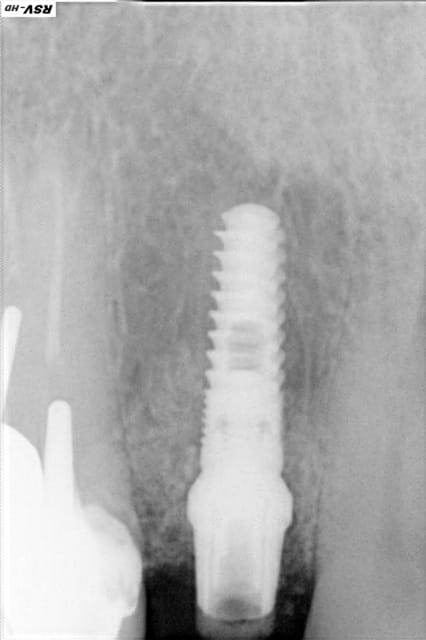

Quelques images de l'année dernière

Imp thgybm - Eugenol